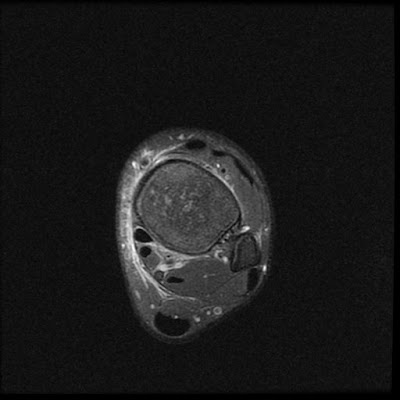

Radial Tear Posterior Meniscal Root

Bucket Handle Tear

Bucket Handle Tear,

Double PCL Sign,